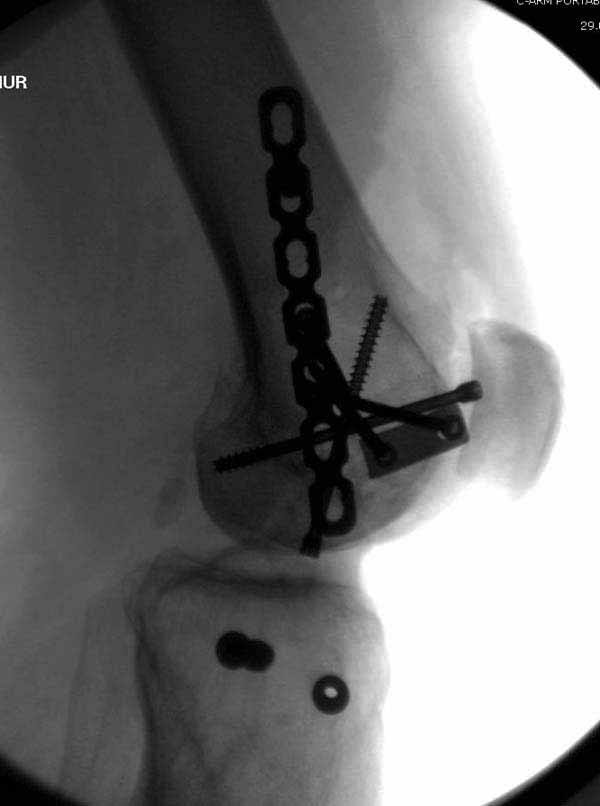

Здесь пример медиальной пластины и латеральный комбинированный метод (у второго больного старый перелом тибиал плато, леченный где то и когда то)

В приложении пример недавней операции, C3, открытая репозиция, фиксация мыщелков спицами и винтами, ретроградный синтез большеберцовым гвоздем 10,5 мм диаметром, винты 5 мм.